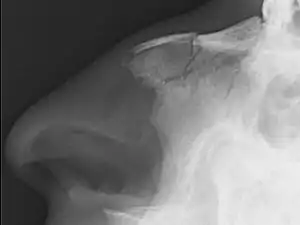

| Plain X-ray showing a nasal fracture | |

Nasal fractures are usually identified visually and through physical examination.[1] Medical imaging is generally not recommended.[1][2] A priority is to distinguish simple fractures limited to the nasal bones (Type 1) from fractures that also involve other facial bones and/or the nasal septum (Types 2 and 3). In simple Type 1 fractures X-Rays supply surprisingly little information beyond clinical examination. However, diagnosis may be confirmed with X-rays or CT scans, and these are required if other facial injuries are suspected.[2]